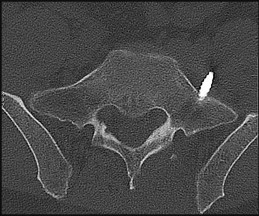

Question 1:

A 45-year-old male presents after a motor vehicle accident with neck pain. Imaging shows a unilateral facet dislocation at C5-C6. What is the most common neurologic deficit associated with this injury if a radiculopathy is present?

Correct Answer: C6 radiculopathy

Explanation:

In a unilateral facet dislocation at C5-C6, the exiting nerve root at that level is C6. The C6 root exits between C5 and C6 in the cervical spine. It is the most commonly injured nerve root in this specific dislocation.